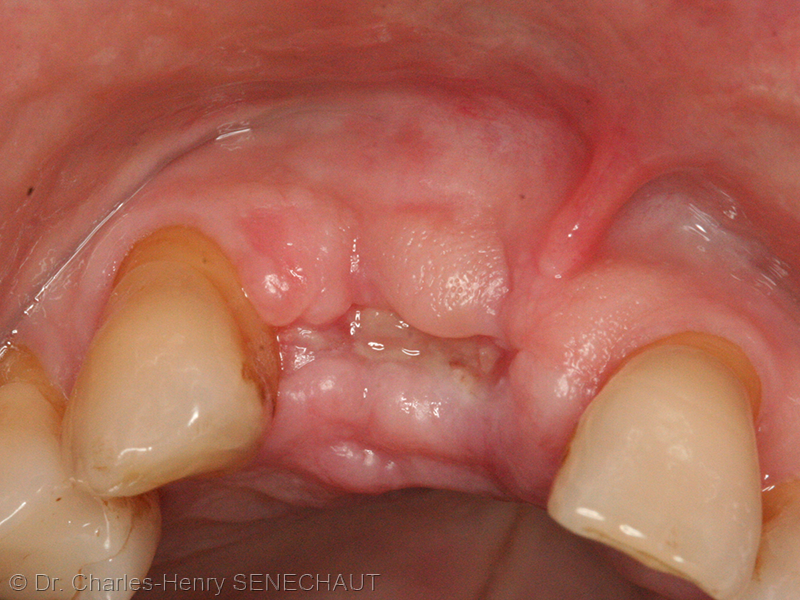

A ce stade l’alvéole est rempli de membranes et de filaments blancs qui sont les cellules mortes du ligament alvéolo-dentaire éliminées.

Revenons à l’alvéole déshabité, une fois la dent extraite.

On peut raboter les pointes osseuses, on décolle un peu la gencive pour pouvoir la tirer, on curette l’alvéole pour retirer les déchets et pour faire saigner, et on met une éponge de collagène imprégnée de thrombase, pour une meilleure formation du caillot sanguin. Le mieux est de poser des points de rapprochement pour serrer les bords gingivaux et fermer la plaie.

Le résultat est déjà meilleur en fin de cicatrisation: